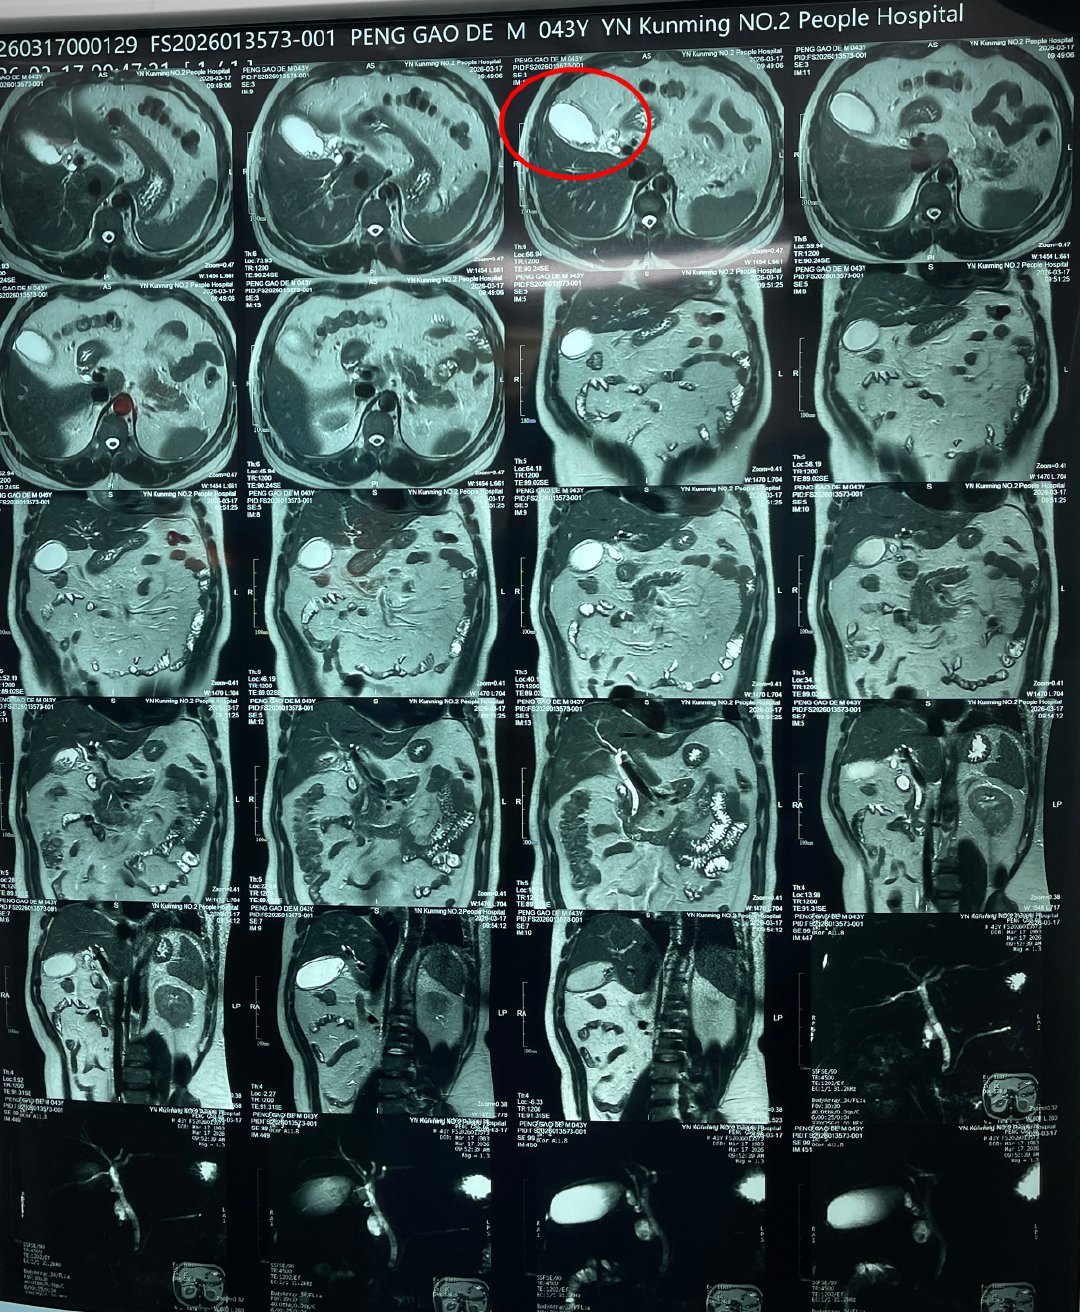

接诊的是肝胆外科王恺主任团队。经详细检查,彭师傅的病情远比想象中危急:胆囊结石伴慢性胆囊炎急性发作,部分胆囊结石掉落至胆总管,引起胆道梗阻、黄疸,导致胆总管结石伴急性化脓性梗阻性胆管炎,并引发了急性胆源性胰腺炎,情况危急。

王恺主任团队立即组织MDT多学科联合会诊,制定手术方案,通过实施微创手术——腹腔镜下胆总管切开探查取石术,精准取出堵塞在胆总管内的结石,帮助彭师傅转危为安。